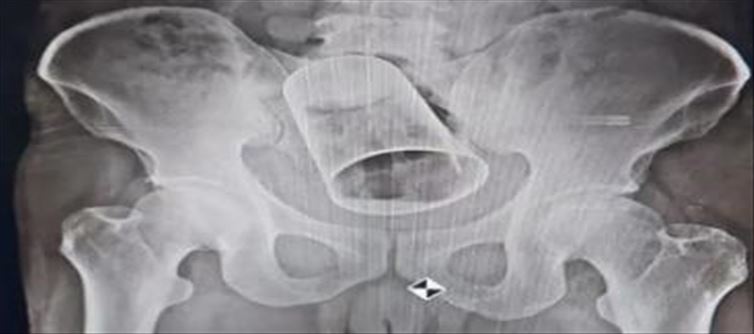

ఇప్పటివరకు అందరూ కలిసి ఎంతో సరదాగా గడిపారు. ఫుల్లుగా మద్యం తాగారు. కానీ ఆ తర్వాత ఒక చిత్రమైన పని చేశారు. ఏకంగా ఒక యువకుడి మలద్వారంలోకి స్టీల్ గ్లాసు చొప్పించారు మిగత స్నేహితులు. ఈ విషయం ఎవరికైనా చెబితే ఏమనుకుంటారో అని బాధితుడు కూడా బయటకి చెప్పలేదు. కానీ నొప్పి తీవ్రం కావడంతో చివరకు ఆస్పత్రికి వెళ్లగా డాక్టర్లు సైతం పరీక్షించి అవాక్కయ్యారు అని చెప్పాలి. ఈ దారుణ ఘటన గుజరాత్లోని సూరత్లో వెలుగుచూసింది. ఒడిశా లోని గంజాం జిల్లాలో బుడుగా బ్లాక్ బలిపాధార్ గ్రామానికి చెందిన కృష్ణా చంద్ర గుజరాత్లోని సూరత్ కి వెళ్లి అక్కడ ఓ కంపెనీ లో పని చేస్తున్నాడు.

ఇటీవలే స్నేహితులతో కలిసి పార్టీ చేసుకున్నాడు. అంతా కలిసి మద్యం తాగారు. మద్యం మత్తులోనే కృష్ణ చంద్ర మలద్వారంలో స్టీల్ క్లాస్ చొప్పించారు. అతనికి నొప్పి మొదలైంది. నొప్పి తీవ్రం కావడంతో సొంతూరికి వచ్చాడు. ఈ క్రమంలోనే విసర్జన కాకపోవడంతో పొట్ట ఉబ్బిపోయి వెంటనే ఆసుపత్రికి వెళ్లగా పరీక్షించిన వైద్యులు అసలు విషయం తెలుసుకొని షాక్ అయ్యారు. చివరికి సర్జరీ చేసి గ్లాస్ బయటికి తీయాల్సిన పరిస్థితి ఏర్పడింది. గ్యాస్ బయటకు తీసేందుకు సుమారు 2.5 గంటల శ్రమించారు వైద్యులు.